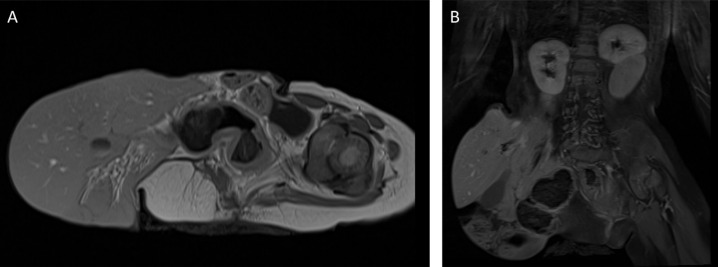

Omphalocele is a congenital abdominal wall defect with herniation of abdominal viscera into a sac. Tc-99m DMSA renal cortical scan is a functional imaging technique used for detecting parenchymal defects, mostly in patients with recurrent urinary tract infection as well as congenital renal abnormalities. Renal anomalies are known to accompany omphalocele. In this retrospective study, we present a case of cephalad renal ectopia as observed on Tc-99m DMSA scintigraphy in a patient with omphalocele due to a large hernia sac containing most of the liver; and we review the renal abnormalities associated with omphalocele in the literature.